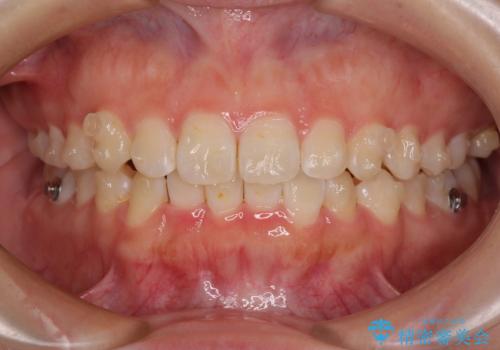

前歯のデコボコを整える インビザラインによる矯正治療

- 上下前歯のデコボコを気にして来院された患者様です。

叢生は軽度であり、ワイヤー矯正でもマウスピース矯正でも対応可能であったので、好きな装置を選んでもらいました。

相談の結果、インビザラインによる矯正治療を行うこととしました。

毎日の装着時間をしっかりと守っていただいたことで、1年程度で無事に治療を終えることができました。